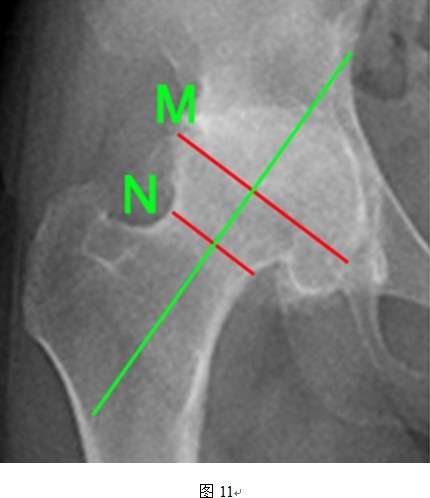

①髋臼角:AB与BD的夹角(A 、B为双侧泪滴投影点,D为髋臼外上缘投影点);

②CE角:CO和OE的夹角(O为股骨头中心点,CO为经过O点的垂线,OE为自股骨头中线点至髋臼外上缘的连线);

③颈干角:GF与OF的夹角(GF为股骨轴线,OF为股骨颈轴线);

④头颈比:M/N的数值(M线为股骨头直径,N线为股骨颈直径);